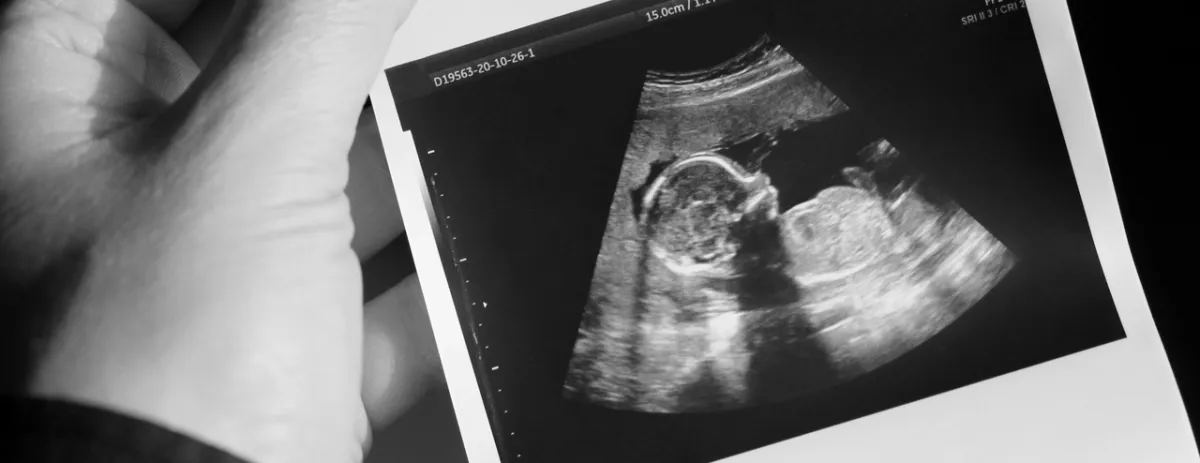

قد يجمع الناس في مجتمعاتنا العربية بين الغثيان والأعراض التي تصيب الحامل في الأشهر الأولى ومصطلح الوحم أو الوحام؛ ولذلك تنتشر بينهم تساؤلات حول الوحام الشديد، ومتى يبدأ الوحم ويختفي، هذا ما يشرحه لك الأطباء والاختصاصيون عن حقيقة هذه الأعراض التي تعانين منها في الحمل.

يبدأ في أوقات مختلفة بين امرأة وأخرى، وعلى الأغلب أن بدايته في الثلث الأول من الحمل، أو في الأسبوع الخامس من الحمل.

وتبلغ شدته في الثلث الثاني من الحمل؛ أي في الشهر الرابع، والخامس، والسادس؛ حيث تشتهي الأم طعاماً ما كل يوم أو يومين، بينما ينخفض في الشهر السابع، والثامن، والتاسع.